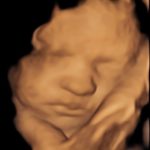

4D/5D/HD Ultrasound Gallery

Gallery